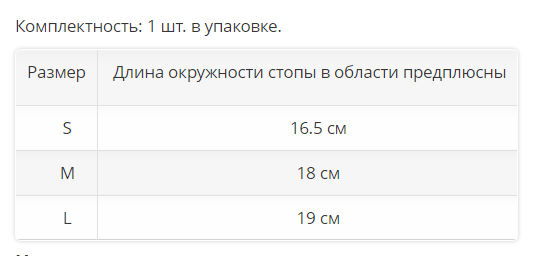

Комплектность: 1 шт. в упаковке.

| Размер |

Длина окружности стопы в области предплюсны |

| S | 16.5 см |

| M | 18 см |

| L |

19 см |